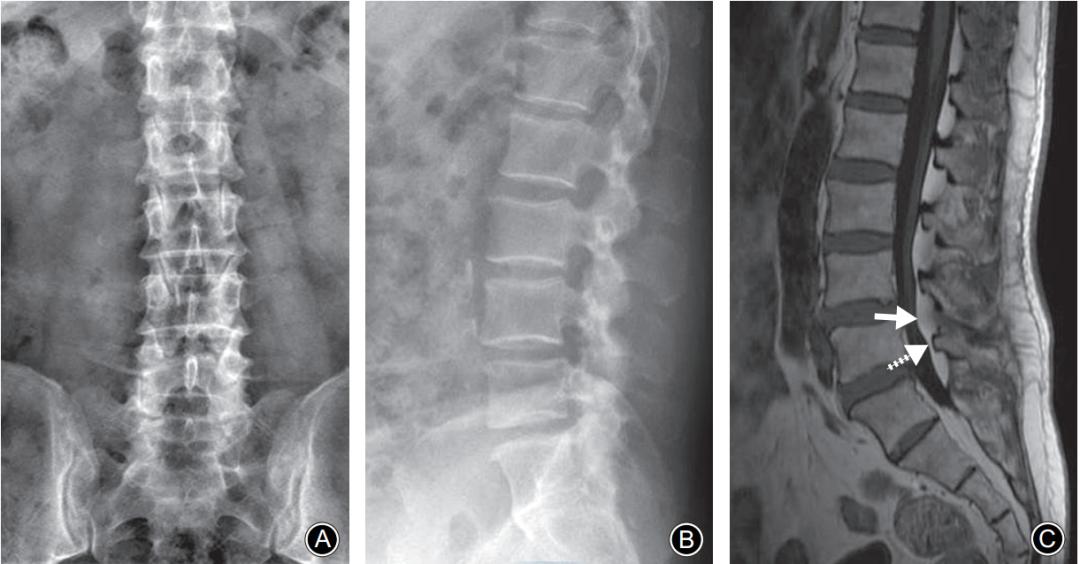

硬膜外脂肪增多症典型病例:男,50岁。A,B: 腰椎正位侧位X线片均无明显椎弓峡部裂征象; C: 腰椎MRI正中矢状面T1WI示L5棘突基底部(虚线剪头) 与硬膜之间出现脂肪高信号带, 伴有L4椎板腹侧弧形脂肪增多 (实线箭头)压迫硬膜。